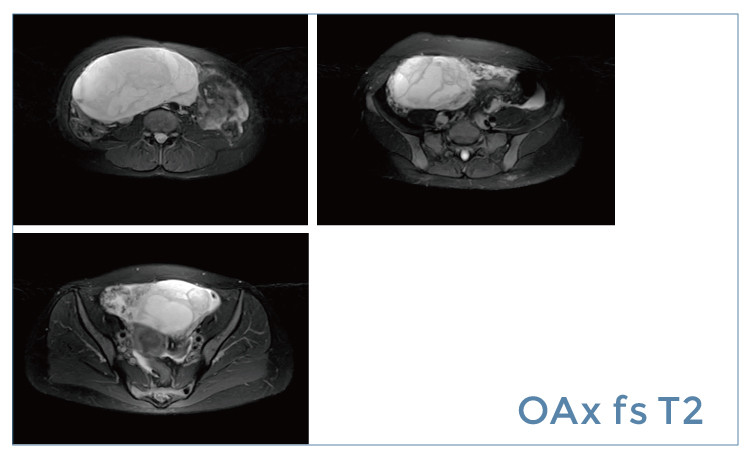

【朗润影像档案】磁共振影像病例分享(编号20190426)

【朗润影像档案】磁共振影像病例分享(编号20190419)

【朗润影像档案】磁共振影像病例分享(编号20190412)

【朗润影像档案】磁共振影像病例分享(编号20190405)